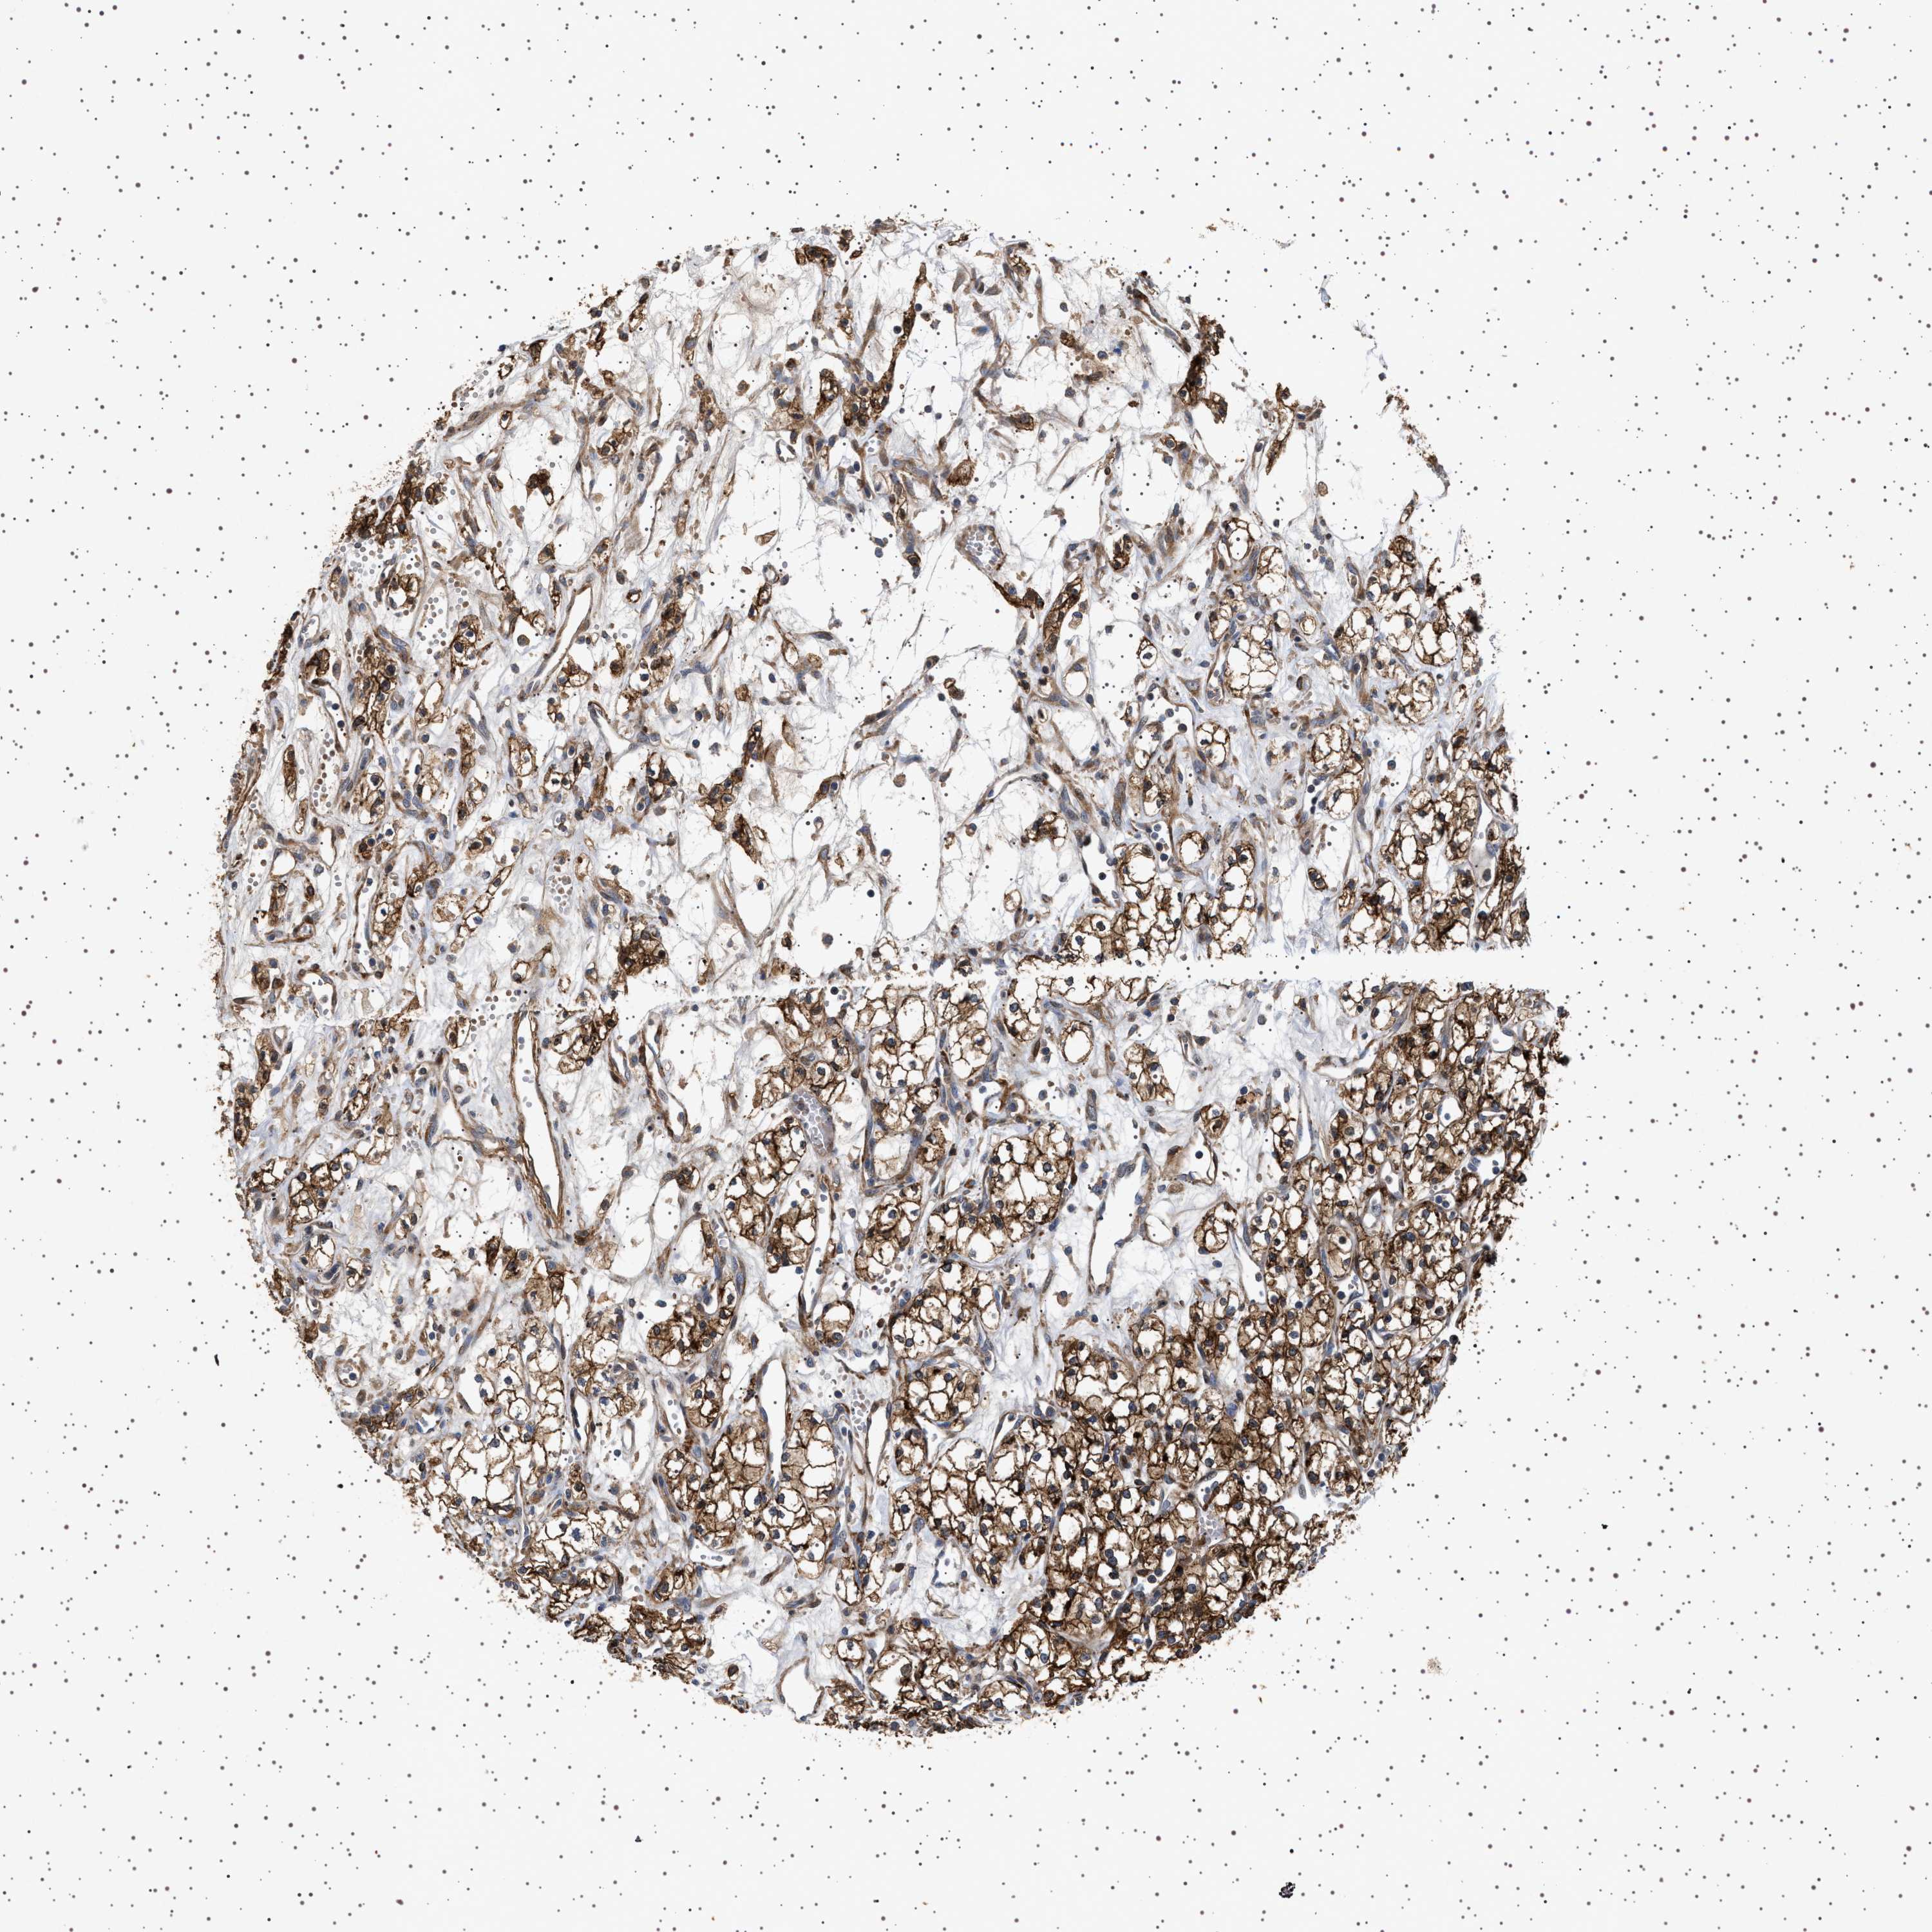

KIDNEY RENAL CLEAR CELL CARCINOMA (TCGA) - Interactive survival scatter ploti

The Survival Scatter plot shows the clinical status (i.e. dead or alive) for all individuals in the patient cohort, based on the same data that underlies the corresponding Kaplan-Meier plots. Patients that are alive at last time for follow-up are shown in blue and patients who have died during the study are shown in red.

The x-axis shows the expression levels (FPKM) of the investigated gene in the tumor tissue at the time of diagnosis. The y-axis shows the follow-up time after diagnosis (years). Both axes are complimented with kernel density curves demonstrating the data density over the axes. The top density plot shows the expression levels (FPKM) distribution among dead (red) and alive patients (blue). The right density plot shows the data density of the survived years of dead patients with high and low expression levels respectively, stratified using the cutoff indicated by the vertical dashed line through the Survival Scatter plot. This cutoff is automatically defined based on the FPKM cutoff that minimizes the p-score. The cutoff can be changed by dragging the vertical line or by entering a cutoff value in the square labeled "Current cut-off".

Under the Survival Scatter plot the p-score landscape (black curve; left axis) is shown together with dead median separation (red curve; right axis). Dead median separation is the difference in median mRNA expression between patients who have died with high and low expression, respectively. It is calculated as follows: median FPKM expression of dead patients with high expression - median FPKM expression of dead patients with low expression. This is intended to aid the user in visually exploring custom cutoffs and the associated p-scores and dead median separation.

Individual patient data is displayed and can be filtered by clicking on one or more of the category buttons on the top of the page. Categories describing expression level and patient information include: high, low, alive, dead, female, male and tumor stages. The scale of the x-axis can be toggled between linear and log-scale by clicking on the "x log" button. Mouse-over function shows TCGA ID, patient information and mRNA expression (FPKM) for each patient.

& Survival analysisi

Kaplan-Meier plots summarize results from analysis of correlation between mRNA expression level and patient survival. Patients were divided based on level of expression into one of the two groups "low" (under cut off) or "high" (over cut off). X-axis shows time for survival (years) and y-axis shows the probability of survival, where 1.0 corresponds to 100 percent.

GUCY1B1 is validated prognostic, high expression is favorable in Kidney Renal Clear Cell Carcinoma (TCGA)

Best expression cut offi

: 26.78

Median expressioni

TCGA RNA samplesi

Average pTPM 32.9

Number of samples 521